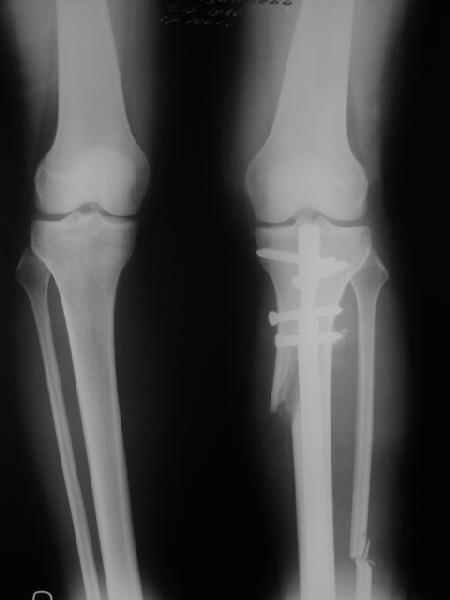

Yesterday one leg was done (my plan to make both in one session were cancelled because of external reasons). So much exciting and useful experience.

The osteotomy line i planned to make a bit oblique, but not so as you suggested. But at the moment of osteoclasis after corticotomy through the anterior stab wound the line became almost as you described. Now problem is how to reproduce thee line at the next leg ;-)

The prominent fragment seems to be useful for cosmetic purposes, because aesthetic guys perform medialization of the distal fragment to gain attractive curve at the medial side of the leg. Also all locking options became available - initially i planned to engage only two most

proximal 45 degree holes.

I cut the fibula because i externally rotated the distal fragment by 6-7 degrees. With only angular correction it didn't show any displacement.

Today CT for estimation of rotation was performed, results i will see only tomorrow. Rotation of the operated limb can be corrected with the second surgery. Comments/critics are welcome.